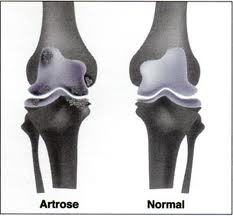

A Artrose no Joelho é uma doença degenerativa das articulações também chamada de Osteoartrite. O problema de natureza inflamatória não tem cura e tem como principal causa o desgaste que ocorre nas cartilagens dos joelhos devido a sobrecarga imposta a essa parte do corpo. Indivíduos devidamente diagnosticados podem ter uma vida normal e saudável seguindo os tratamentos recomendados por um especialista.

O desenvolvimento dessa doença se dá pelo desgaste das cartilagens responsáveis por revestir as extremidades ósseas de forma a causar muita dor e até mesmo deformações. A incidência de Artrose no Joelho é bastante comum porque as articulações do joelho estão dentre as articulações mais afetadas pela sobrecarga de peso.